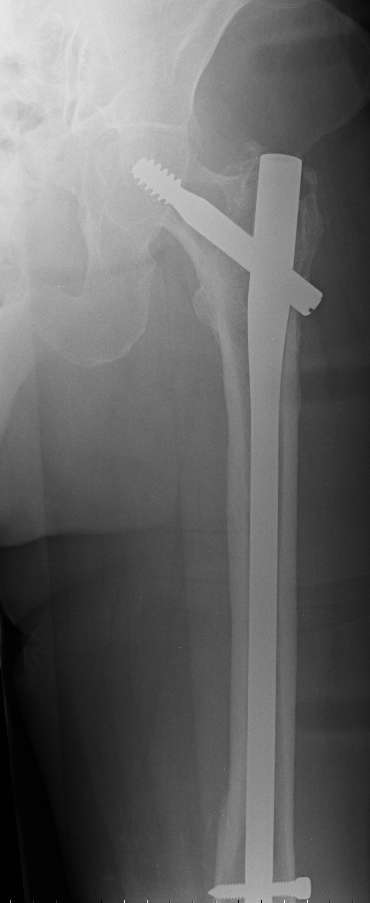

Dear All, I should like know what is your preferred treatment for this fracture at the tip of a long Gamma nail (on a healed subtrocantheric fracture : see img).

The patient is a 81 years old lady with osteoporosis and important knee arthrosis (as you can see).

Do you remove the nail or not? can we obtain a stable ostheosynthesis with a plate without remove the nail?

Do you prefer to apply a plate or an endomedullary nail (along the old way of gamma nail) to preserve joint motion?

It is justified to apply bone cement in the bone loss ?